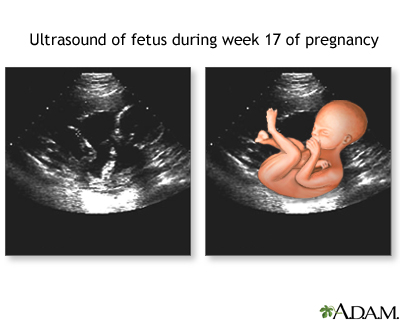

- Pregnancy